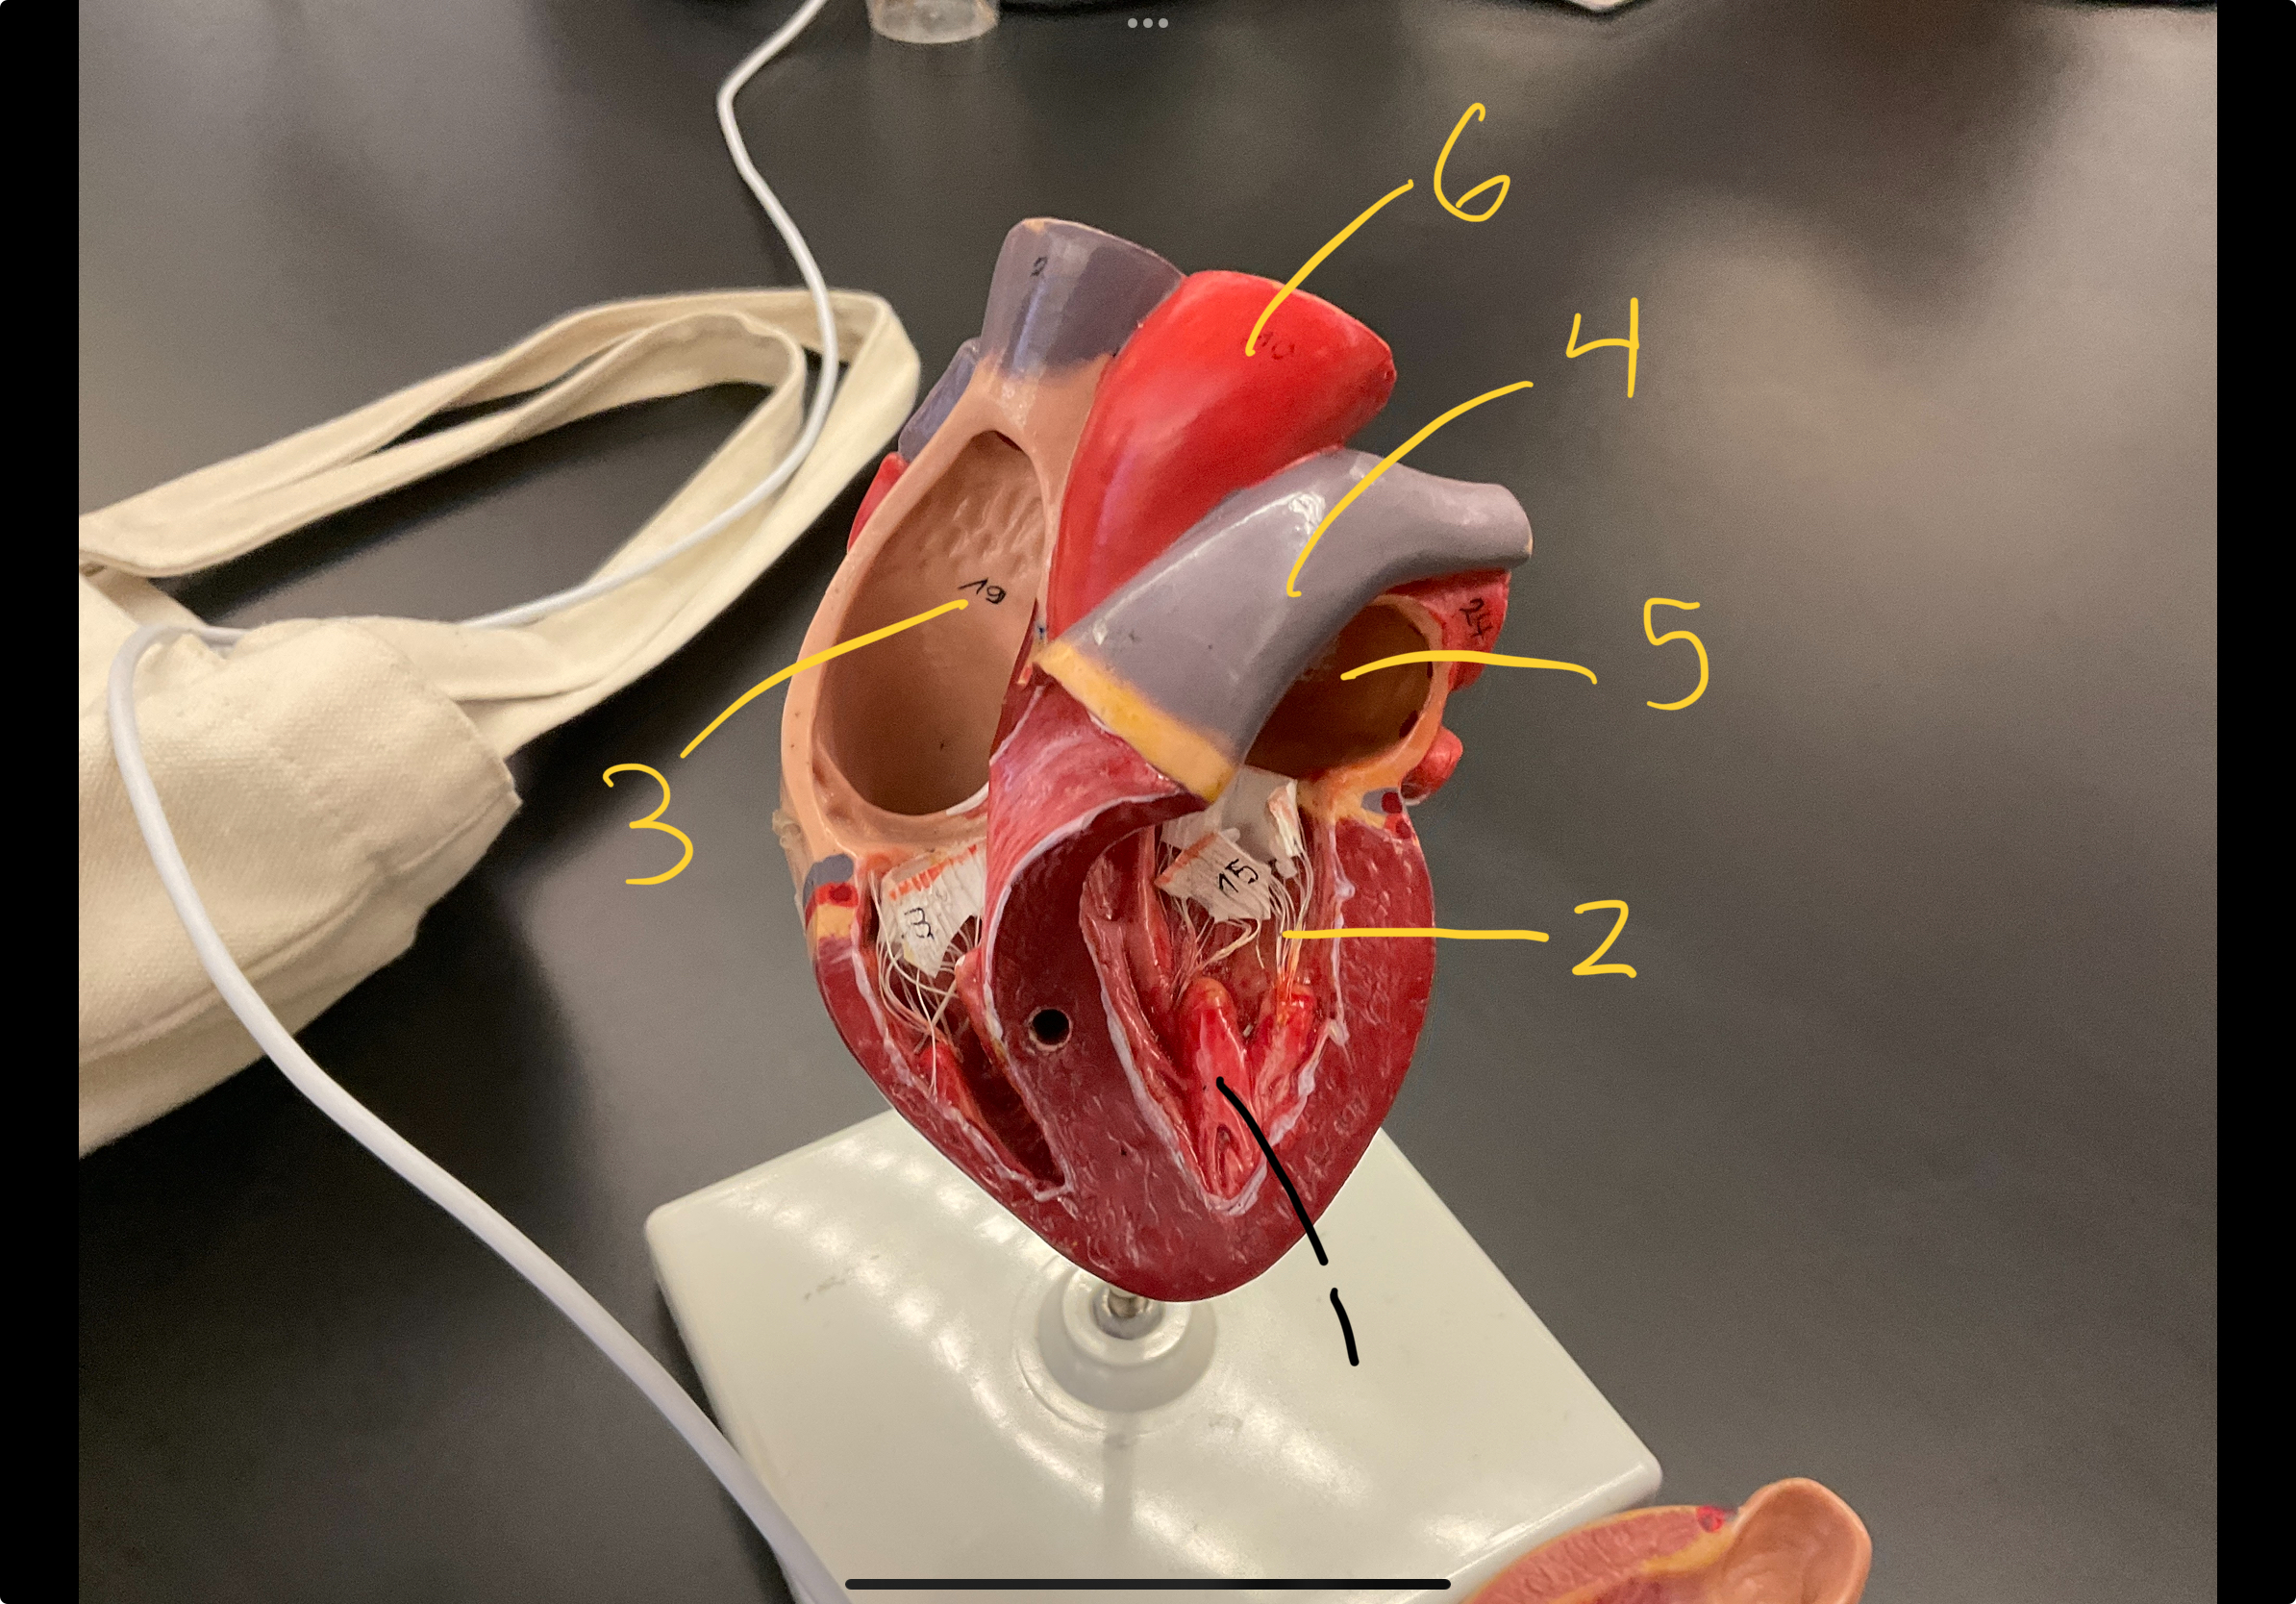

1

epicardium

2

3

endocardium

3

2

myocardium

4

1

coronary sinus

5

2

inferior vena cava

6

3

superior vena cava

7

1

right ventricle

8

2

left ventricle

9

3

bicuspid

10

4

tricuspid

11

5

interventricullar septum

12

6

left atrium

13

7

aorta

14

8

aortic trunk

15

9

pulmonary semi-lunar valve

18

1

papillary muscle

19

2

chordae tendineae